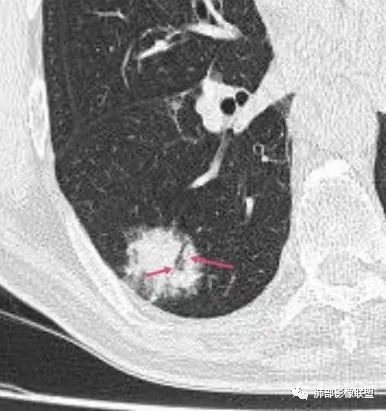

老年男性,右肺下叶混合磨玻璃密度结节,可见血管弯征,首先考虑肺腺癌。

右肺下叶背段不规则结节,边界欠清,可见少许晕征,另见胸膜凹陷征及血管弯,考虑腺癌,鉴别隐球菌。

右肺下早不规则结节,周围少许磨玻璃晕,胸膜有牵拉凹陷,虽然部分边界平直,但血管受牵拉弯曲,首先还是考虑肿瘤,腺癌

右肺下叶背段斑片影,边缘平直、局部膨隆,可见磨玻璃密度影,界清,胸膜牵拉,良恶性需要进一步鉴别,倾向隐球,鉴别粘液腺癌。

老年男性,右肺下叶胸膜下结节,边缘见清晰磨玻璃密度影及少许索条,支气管进入后截断,周围血管弯,考虑腺癌,鉴别隐球菌

右肺下叶胸膜下混合密度结节,分叶、毛刺,磨玻璃边界尚清晰,血管集束,支气管进入阻断,考虑腺癌

右肺下叶背段胸膜下肿块,边缘不规则,分叶,毛刺,有磨玻璃,边界清,近肺门侧见血管聚集,支气管进入后闭塞,右肺下叶肺静脉牵拉扭曲。诊断,支持腺癌

老年患者,无呼吸道相关症状,肺部影像学表现:胸膜下占位,有结节融合趋势,内有低密度灶。考虑隐球菌,鉴别腺癌。

胸膜下结节,与胸膜平行,多结节融合,边缘模糊,直边征,考虑炎性肉芽肿,隐球,腺癌

右肺下叶背段实性结节,边缘分叶,较平直,长轴平行胸膜,胸膜增厚,考虑炎性假瘤,隐球菌,鉴别腺癌。

混合性磨玻璃结节,边界清晰,血管打弯,考虑腺癌,鉴别炎性肉芽肿病变。

老年男性,体检发现,无症状,右肺下叶背段肿块影,边缘清楚,无卫星灶,棘状突起,毛刺征,血管集支束,空泡征,考虑恶性肿瘤。

老年男性,体检发现。右肺下叶混合磨玻璃结节,渗漏征,短毛刺,血管集支束,空泡,考虑腺癌。

老年男性右肺下叶靠近胸膜一不规则混合密度影,周围有渗出,内见支气管扩张,考虑炎性病变隐球鉴别腺癌

老年男性 右肺下叶胸膜下见一团状实性病灶+边缘磨玻璃,边缘形态不规则,,局部有平直,长轴平行于胸膜面,整体收缩力偏弱,邻近胸膜面轻度增厚,纵隔窗显示病灶内可见支气管充气,考虑炎性肉芽肿,隐球菌可能,鉴别黏液腺癌。

右肺下叶实行病灶,边缘部分有边界清晰的磨玻璃影,实变明显层面,可见平直。考虑腺癌

右下肺近胸膜病变,周围可见磨玻璃影,界限无法判断清楚?模糊?。考虑右下肺占位:真菌感染?腺癌?淋巴瘤?

右肺下叶胸膜下结节,边界清楚毛玻璃,有分叶、毛刺、血管集束及胸膜增厚,考虑肉芽肿性病变,鉴别于腺癌

右肺下叶实性病灶,局部平直,考虑炎性病变,隐球菌可能

胸膜下结节,长轴与胸膜平行,边缘模糊,直边征胸膜凹陷牵拉不明显,考虑炎性肉芽肿,隐?鉴别腺癌。

右肺下叶后基底段胸膜下斑块影,边缘清楚,有平直和膨隆特点,周围清楚GGO,较模糊(似清非清,邻近见多发纯GGO结节,以肺腺泡分布,主体病灶与胸膜平行,收缩力弱,边缘见支气管充气征,首诊断炎性肉芽肿,抗炎治疗和查下隐球荚膜抗原两方面进行,另取旧片对比,与粘液腺Ca鉴别,最后经皮肺穿刺病理诊断!

上面这些征象存在炎性病变可能,我先考虑炎性病变——隐球,这样的血管弯在肺隐球菌病里也出现过。腺癌尤其是粘液腺癌也不敢排除。建议完善血隐球菌荚膜抗原、经皮肺穿刺活检等检查。

结节型粘液腺癌,具有血管弯,支气管截断,磨玻璃边界清楚等恶性征象,同时磨玻璃内部较糊,似清非清,不符合普通腺癌附壁生长特点,更像局限的粘液成分。收缩力不强,胸膜局部微积液,内部小空洞(考虑局部粘液排除形成),所以考虑结节型粘液腺癌。